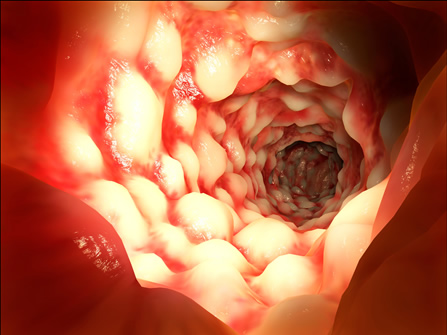

Η νόσος Crohn περιγράφηκε για πρώτη φορά το 1932 από τον Burrill Β. Crohn και τους συνεργάτες του στο Νοσοκομείο Mount Sinai της Νέας Υόρκης. Οι ασθενείς με νόσο Crohn έχουν μία εφόρου ζωής φλεγμονή του γαστρεντερικού σωλήνα, η οποία ξεκινά από την εσωτερική επένδυση του τοιχώματος του, που είναι γνωστή ως βλεννογόνος, και, συνήθως επεκτείνεται και στα βαθύτερα στρώματα του. Η περιοχή στην οποία πιο συχνά αναπτύσσεται η φλεγμονή είναι το σημείο της ένωσης του λεπτού με το παχύ έντερο, δηλαδή εκεί που ο τελικός ειλεός, το τελευταίο τμήμα του λεπτού εντέρου, ενώνεται με το πρώτο τμήμα του παχέος εντέρου, που ονομάζεται τυφλό.

Βαριά προσβολή από νόσο Crohn σε κολονοσκόπηση

Η παρουσία φλεγμονής στο βλεννογόνο του εντέρου, στένωσης ή στομίου από συρίγγιο, μαζί με τα αποτελέσματα από τις βιοψίες που θα ληφθούν κατά την κολονοσκόπηση, θα βοηθήσουν στην επιβεβαίωση της διάγνωσης και θα επιτρέψουν στο γιατρό να προσδιορίσει την έκταση του εντέρου που πάσχει από τη νόσο Crohn. Τα ευρήματα θα χρησιμοποιηθούν για το σχεδιασμό του χειρουργικού πλάνου, εφόσον αποφασιστεί χειρουργική παρέμβαση.